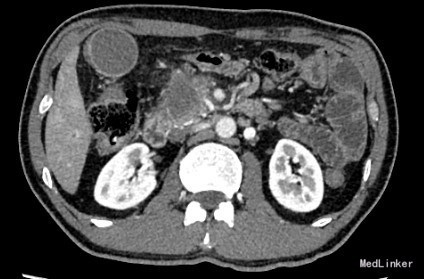

查体:身目重度黄染,上腹部轻压痛; 辅助检查: 白细胞WBC:10.96; 血红蛋白Hb:145g/L;血小板PLT:241x10^9/L 丙氨酸氨基转移酶ALT 357 U/L ;天冬氨酸氨基转移酶AST 191 U/L;白蛋白ALB 40.9 g/L ;总胆红素TBIL 151.2 umol/L;直接胆红素DBIL 85.8 umol/L 肿瘤标记物: 甲胎蛋白(AFP) 5.00 ug/L 0.00 - 20.00 ;癌胚抗原(CEA) 9.19 ug/L ↑ 0.00 - 5.00 ;CA125 71.00 U/mL ↑ 0.00 - 35.00 鳞癌抗原(SCC) 0.90 ug/L 0.00 - 1.50 ;CA19-9 〉12000.00 U/mL CT:平扫胰体尾部萎缩,胰头区不规则肿大,局部可见类圆形软组织肿块影,大小约44×43mm,边界模糊,内部密度不均,其内可见斑点状钙化灶,并见更低密度区。增强扫描正常胰腺组织明显强化而肿物轻度强化,显示较清楚;强化不均匀,中央有低密度坏死区。肿块与十二直肠降段分界不清,病变包绕肠系膜上静脉,血管见充盈缺损影,胰头周围及腹膜后见肿大的淋巴结影。、、、 1.胰头癌,侵犯十二指肠降段及肠系膜上静脉,胰周及腹膜后多发淋巴结轻度肿大。 2.肝S7病灶,高度怀疑转移瘤。 超声造影提:胰头病变:考虑胰头Ca。 肝S7病变:考虑MLC。 肝内外胆管弥漫性扩张。胆囊壁增厚。腹膜后淋巴结肿大。脾脏超声检查未见异常。